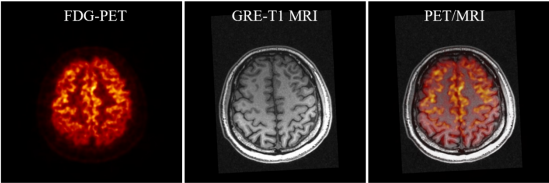

SIAT bPET和联影uMR790 3T磁共振成像系统上同时获得的人脑PET/MRI图像

杨永峰介绍道,与国外商业磁兼容脑PET成像仪器相比,SIAT bPET的效率提高了近2倍(从7.2%到14%),平均体分辨率提高了30倍以上(从约64mm3到2mm3)。同时,SIAT bPET采用了创新的电子学和磁兼容设计,使得磁共振成像对PET成像的影响几乎可以忽略不计,PET成像对磁共振成像图像信噪比的影响小于5%,满足同时开展PET/MRI成像的尖端科研需求。

据了解,PET和MRI都是脑科学研究和脑疾病诊断的重要工具,PET的高灵敏度、高定量精度功能代谢成像和MRI的高空间分辨率、高软组织对比度解剖结构成像高度互补,PET和MRI还可以相互辅助,进一步提升各自的脑神经成像能力。PET分子成像通过测量大脑的血流、葡萄糖和氧的代谢、蛋白质的生成、药物的分布和神经递质的动力学等,探索不同脑区的功能,确定病变脑区的功能演变,对于脑疾病干预治疗策略和新药物探索具有重要意义。